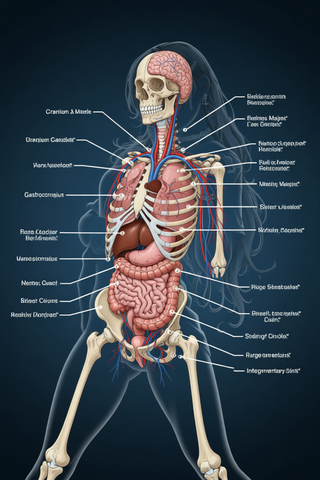

Creates ultra-detailed, multi-layer 3D anatomical visualizations from reference photos.Open

Creates ultra-detailed, multi-layer 3D anatomical visualizations from reference photos.Open

Transform photos into scientific anatomical illustrations.Open

Transform photos into scientific anatomical illustrations.Open